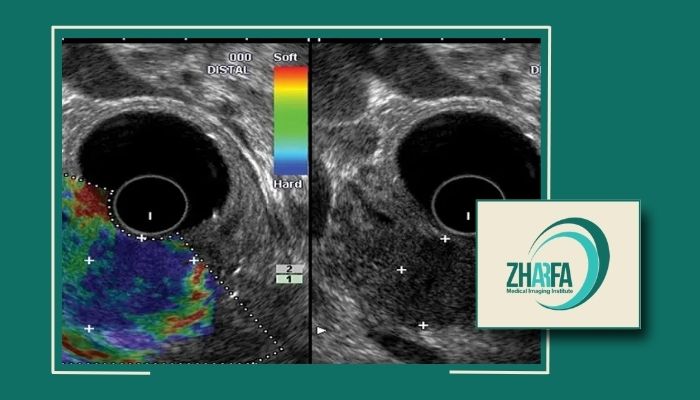

الاستوگرافی فشاری: با اعمال فشار ملایم پروب تغییر شکل بافت سنجیده میشود و نتیجه به شکل نقشه رنگی نسبی است.

تفسیر نتایج سنجش سفتی تودههای پستان

الگوهای نرم و یکنواخت بیشتر احتمال وجود ضایعات خوشخیم مثل کیستهاست.

الگوهای سفت و نامنظم نیازمند بررسی دقیقتر و گاهی نمونهبرداری هستند.

تفسیر مقادیر باید توسط رادیولوژیست و با توجه به سونوگرافی خاکستریاسکیل و سابقه بیمار انجام شود.

یادآوری: تصمیم نهایی درباره خوشخیم یا بدخیم بودن یک توده همیشه با ترکیب معاینه، تصویربرداری و در صورت نیاز پاتولوژی گرفته میشود.